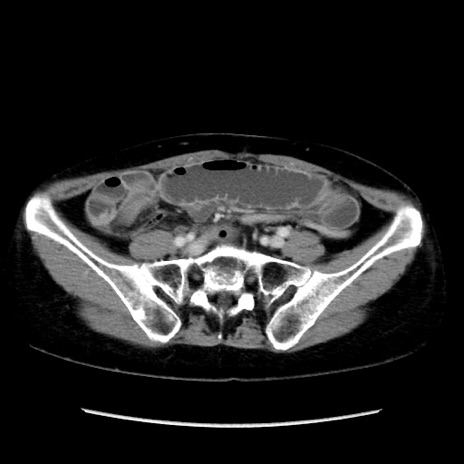

【症例】40歳代 女性

【主訴】上腹部痛、嘔気・嘔吐

【現病歴】約9時間前頃から急に上腹部痛、嘔気、嘔吐が出現。改善しないため救急要請。

【既往歴】子宮頚癌(広汎子宮全摘術、放射線療法)、腸閉塞

【身体所見】腹部:平坦、軟、腸雑音亢進、上腹部を中心に腹部全体に圧痛あり。

【データ】WBC 8400、CRP 0.03